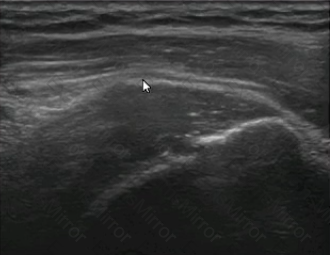

The orthogonal images of a supraspinatus tendon shown here are MOST consistent with which of the following?